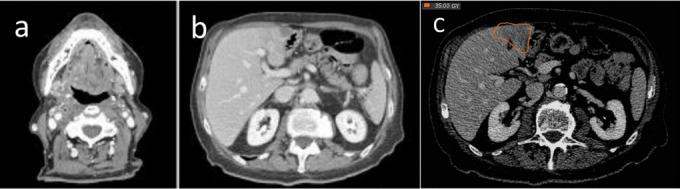

At presentation, isolated metastasis from oropharyngeal squamous cell carcinoma is rare. Liver is a relatively uncommon first site of failure, especially in the absence of other distant metastases, particularly without diagnosis of lung metastases. We report on a case of HPV-related oropharyngeal squamous cell carcinoma with synchronous liver metastasis treated with radiation therapy. This condition, defined as "oligometastatic state," describes a subset of patients with limited volume metastatic disease in whom favorable outcomes were reported with the use of local ablative therapies on both the primary tumor and metastatic sites. As a definitive treatment, we offered the patient, ineligible for other therapeutic approaches, exclusive radiation treatment on the head and neck region and a stereotactic ablative approach targeted to the liver metastasis.

摘要

就诊时,口咽鳞状细胞癌的孤立性转移很少见。肝脏是相对不常见的首个失败部位,尤其是在没有其他远处转移的情况下,特别是未诊断出肺转移时。我们报告了1例接受放射治疗的HPV相关口咽鳞状细胞癌伴同步肝转移的病例。这种情况被定义为“寡转移状态”,描述了一组转移病灶体积有限的患者,据报道,对这些患者的原发肿瘤和转移部位采用局部消融治疗可取得良好疗效。作为确定性治疗,我们为不符合其他治疗方法条件的患者提供了针对头颈部区域的单纯放射治疗以及针对肝转移的立体定向消融治疗。